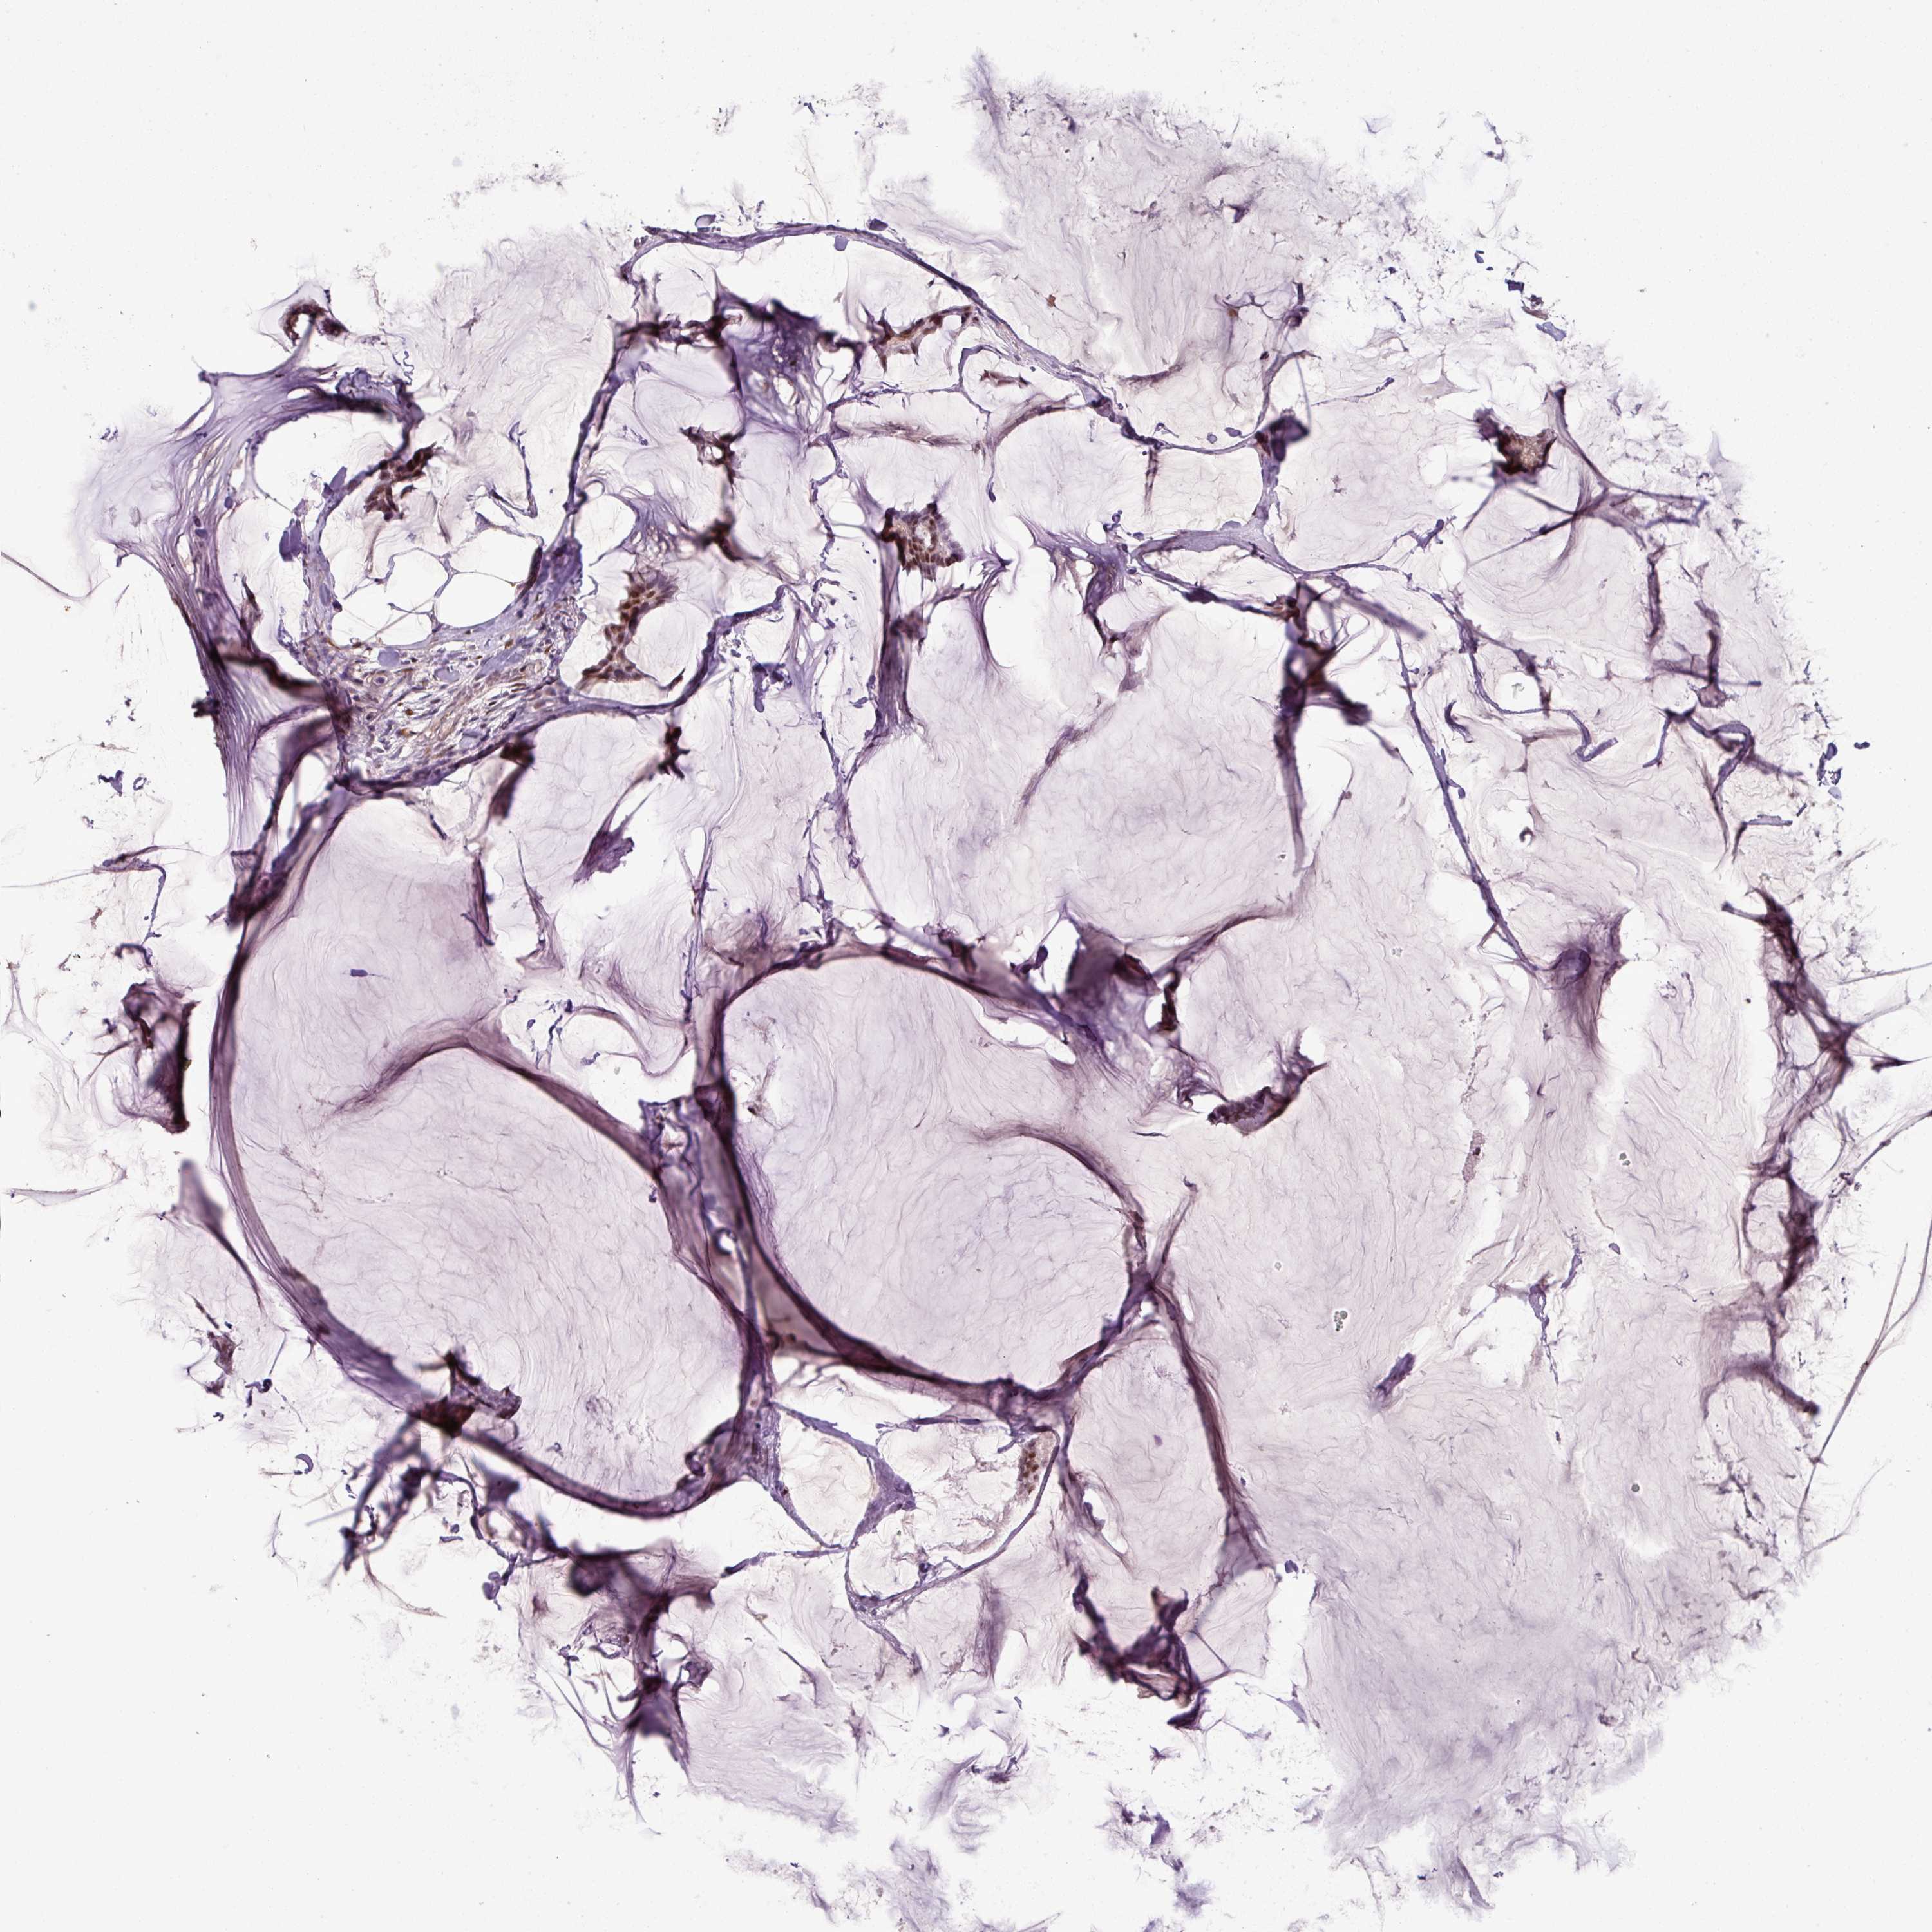

BRCA TCGA BRCA VALIDATION PROTEIN EXPRESSION

ANTIBODIES

AND

VALIDATION